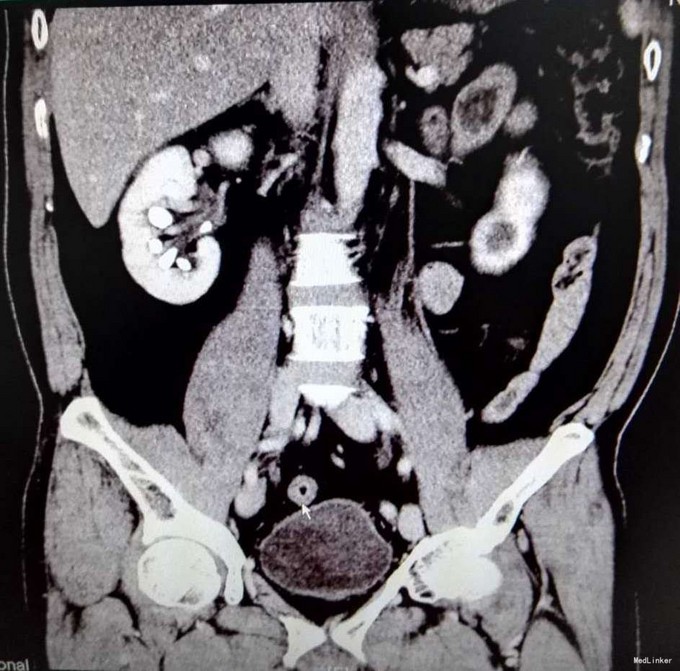

3、查体:未见明显阳性体征 4、辅助检查:外院平片:双肾多发结石;我院CTU:双肾多发结石,左侧肾盂输尿管连接处结石,并双肾积水,左肾明显,双侧肾盂、输尿管炎症。

5、诊断:肾结石(双肾多发结石) 6、治疗:入院后完善相关检查,双肾CTU:双肾多发结石,左侧肾盂输尿管连接处结石,并双肾积水,左肾明显,双侧肾盂、输尿管炎症。排除手术禁忌症后行左侧PCNL术,术后恢复良好,拔出肾造瘘管后,先出院休息,2周后返院进一步治疗